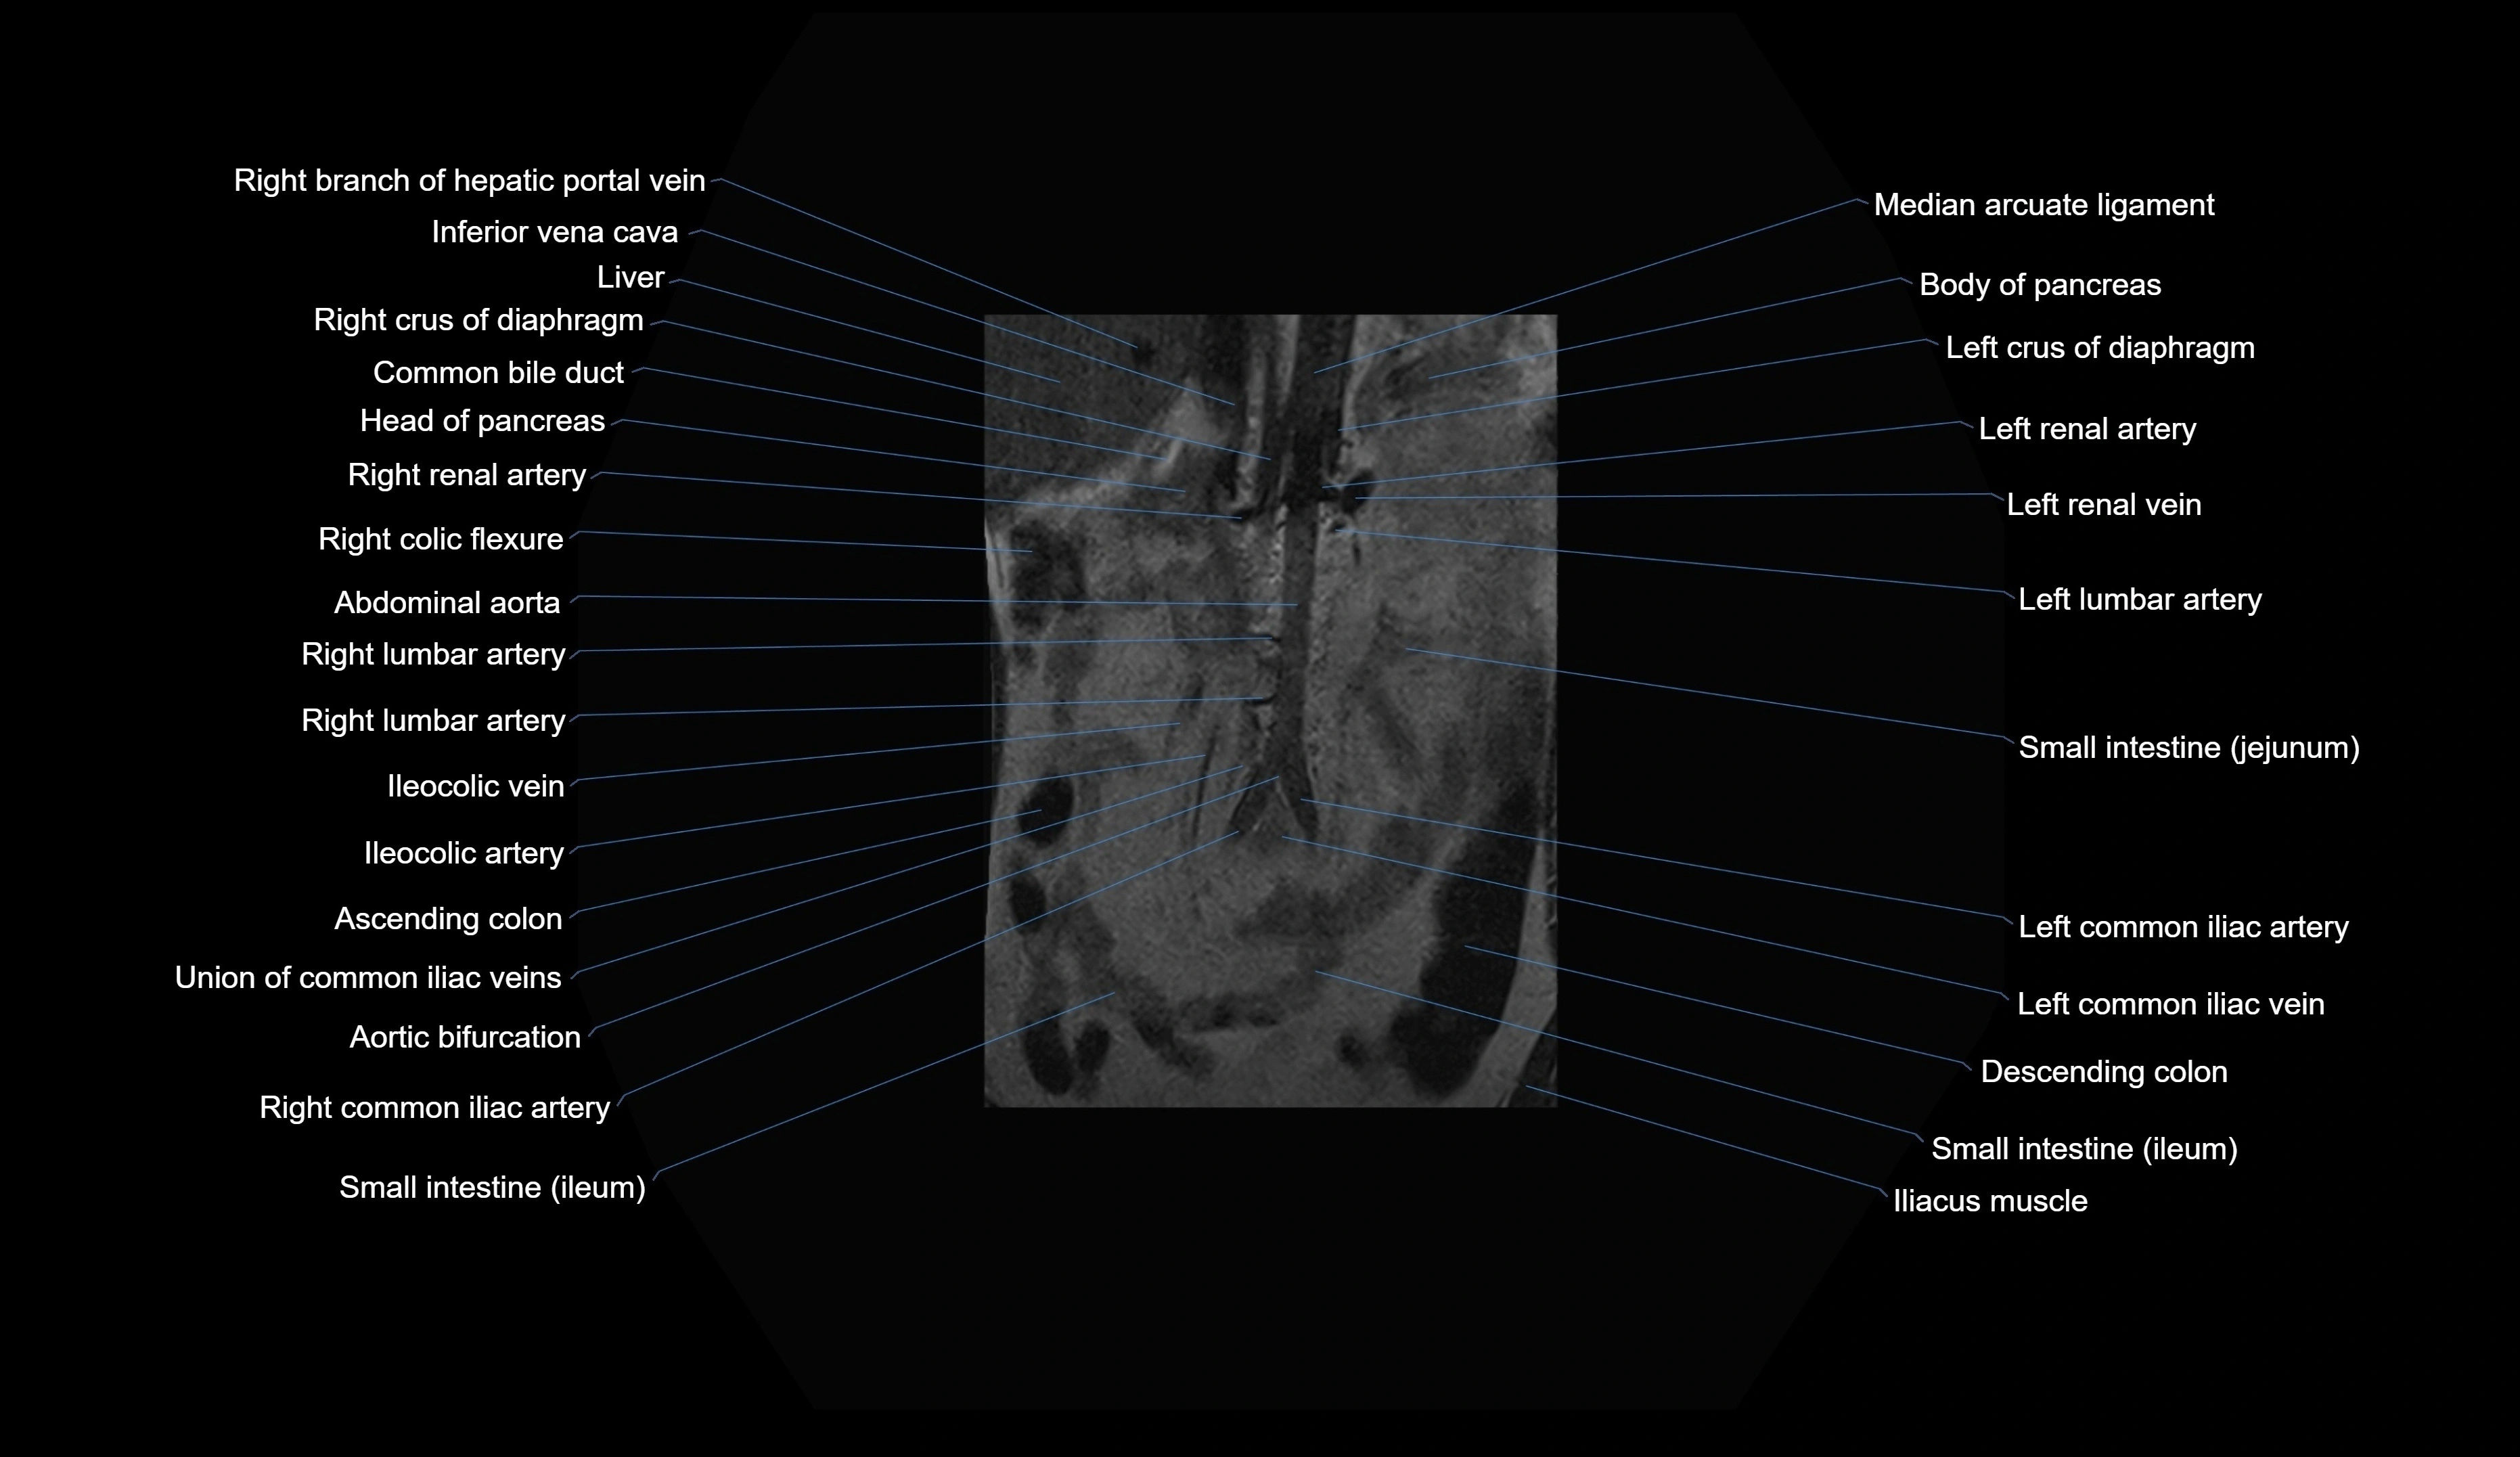

CT images